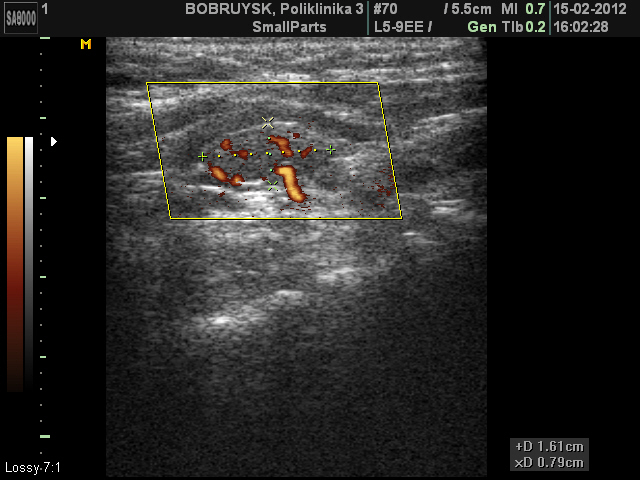

Вот такой ультразвуковой случай образования в проекции щитовидной железы.

Пациентка 66 лет. Жалоб не предъявляет

Стоит на учете у эндокринолога, диагноз не помнит, но говорит узел какой то года три назад, пунктировали, но результатов не знает и не помнит.

ADENOMA_5.JPG

ADENOMA_11.JPG

Первое впечатление - ХАИТ, псевдоузловая форма.

Я конечно же не "свадебщик", по этому в данном случае, рассматриваю вариант с аденомой паращитовидной железы. Хотя структура самой щитовидной железы, которая мной отражена не достаточно хорошо в ролике, действительно похожа на АИТ.